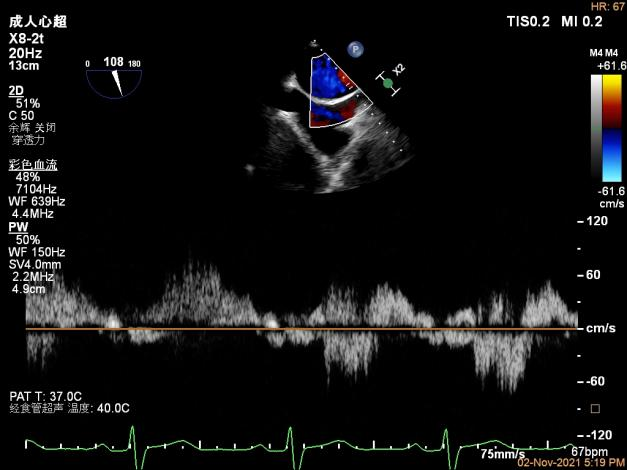

术前超声评估结果

3D-color MV view:大量反流,起源于1区

X-plane:下夹子尝试先捕获1区脱垂瓣叶

夹子关闭过程中,Color提示1区反流逐渐减少

二尖瓣口平均跨瓣压差:2mmHg

肺静脉血流频谱恢复正向